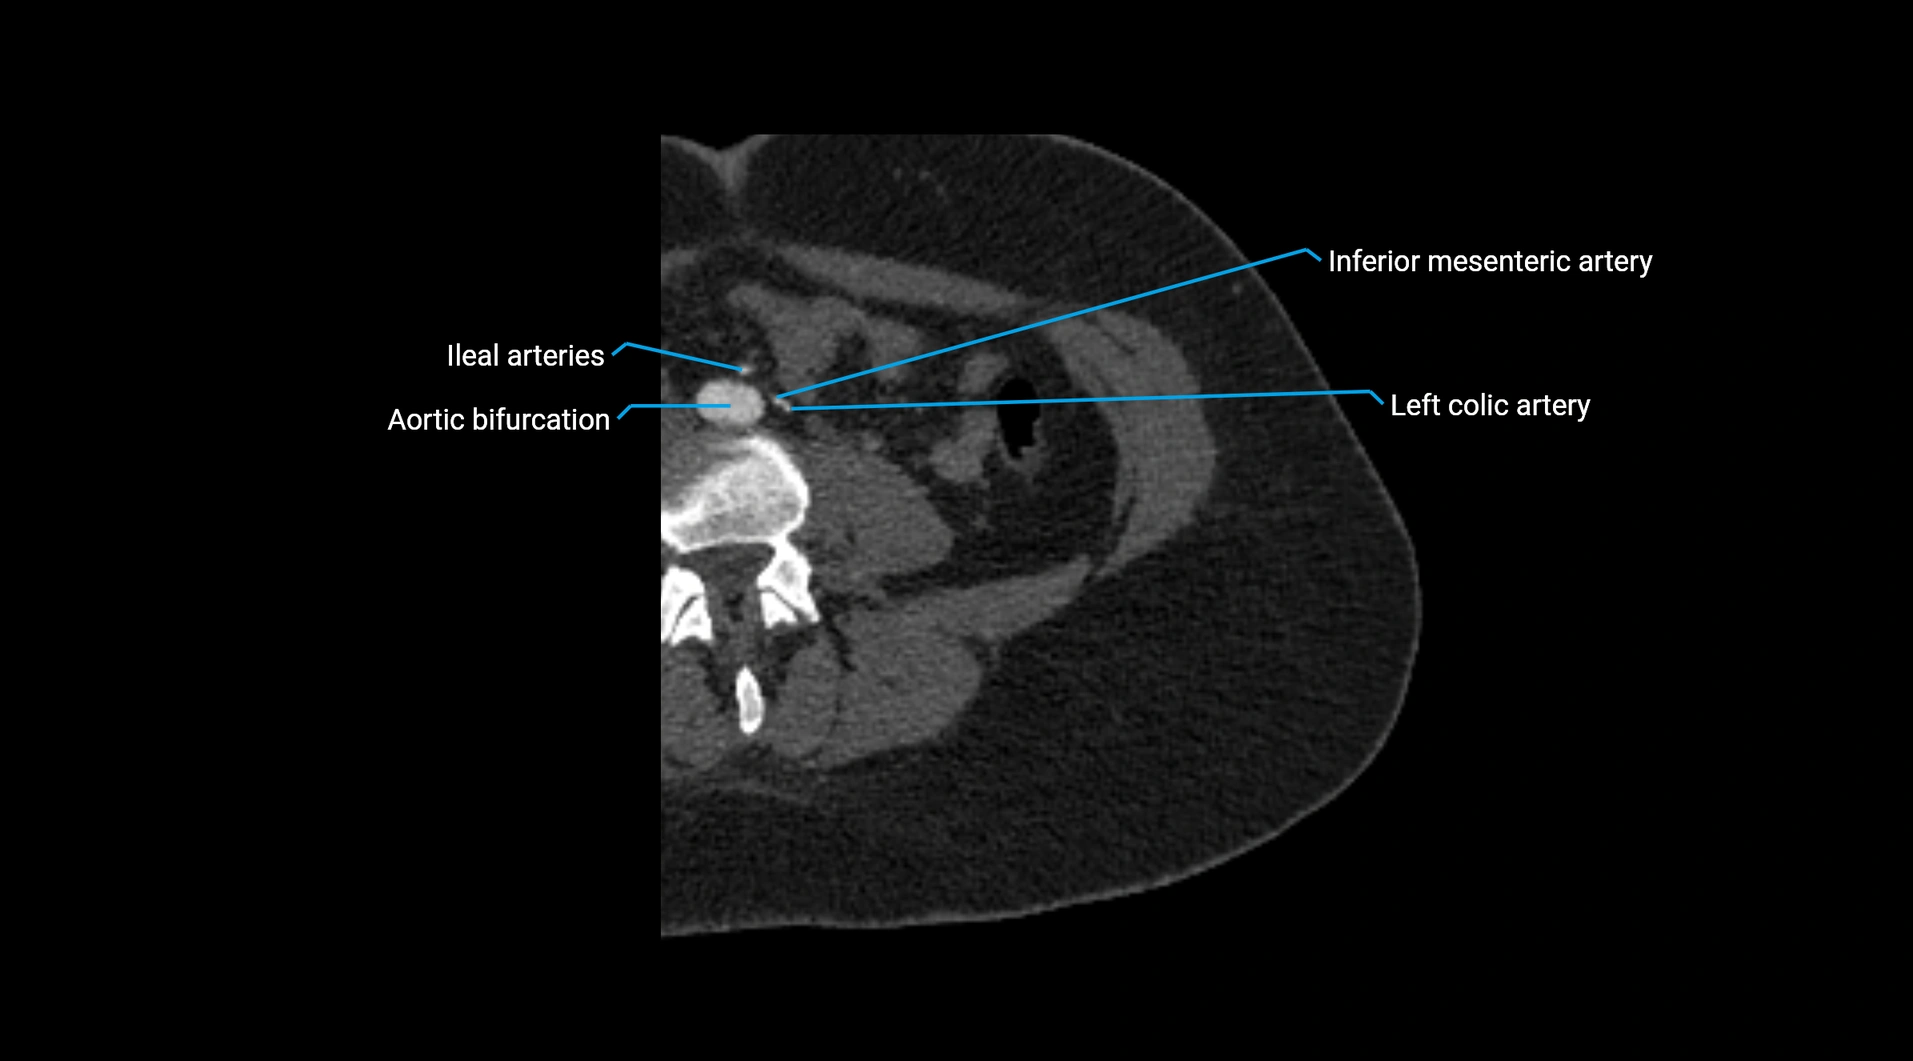

CT images

image